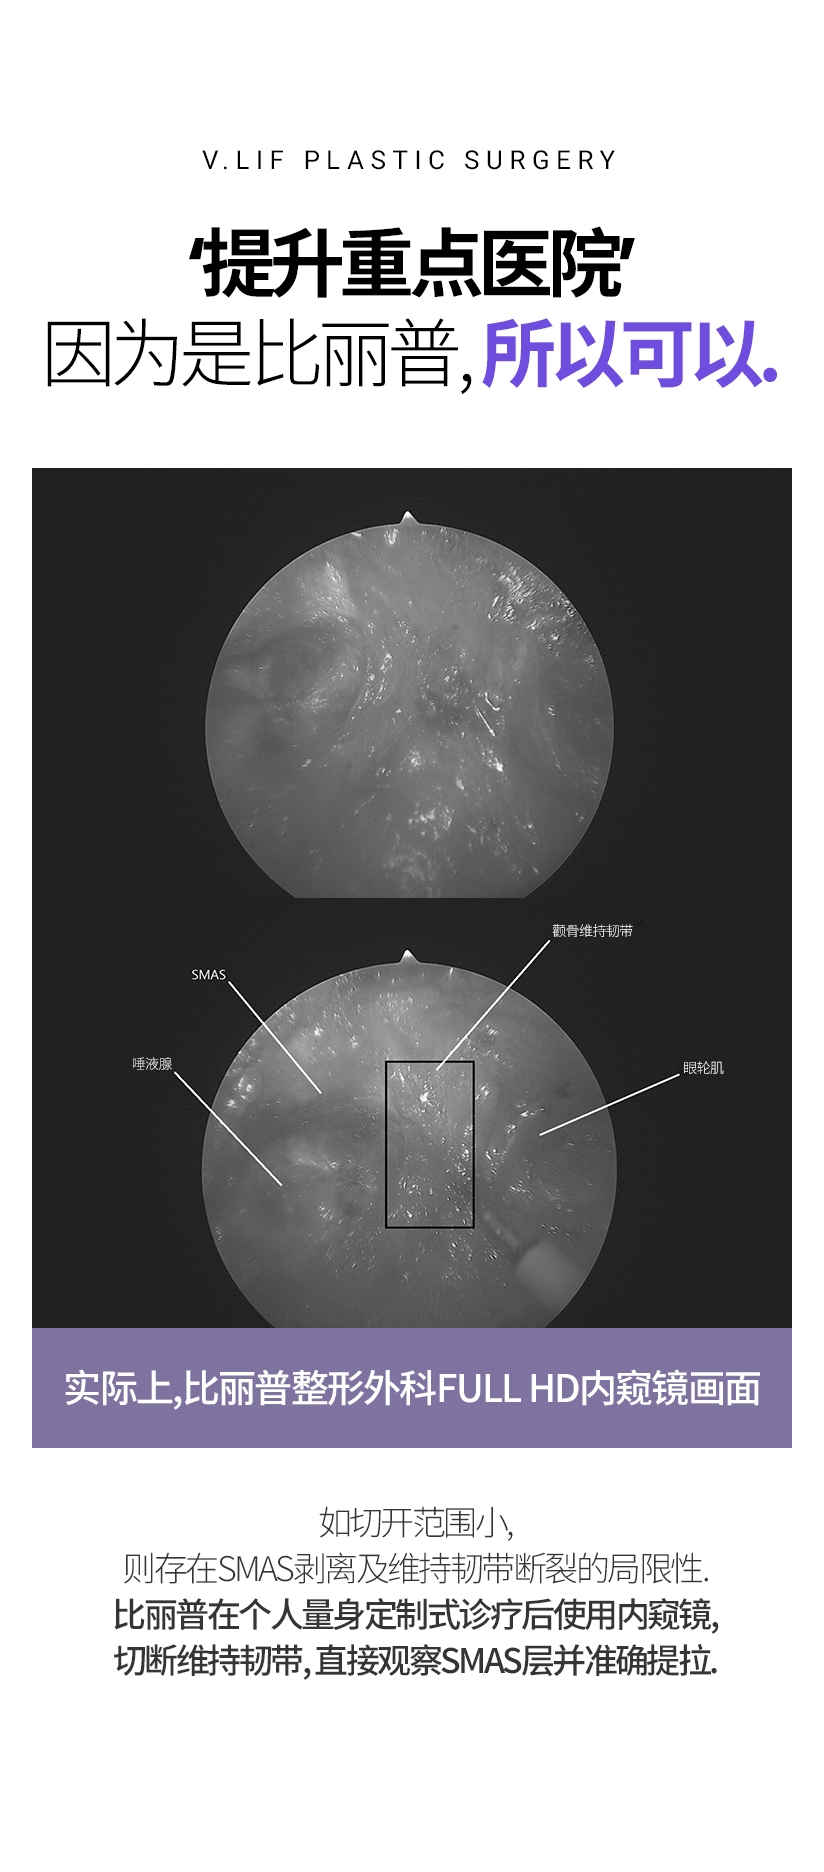

‘提升重点医院’ 因为是比丽普, 所以可以. 实际上, 比丽普整形外科 FULL HD 内窥镜画面 实际上, 比丽普整形外科 FULL HD 内窥镜画面 如切开范围小, 则存在SMAS剥离及维持韧带断裂的局限性. 比丽普在个人量身定制式诊疗后使用内窥镜, 切断维持韧带, 直接观察SMAS层并准确提拉.